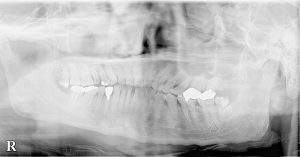

口腔外科(インプラント)、歯科・矯正歯科(歯列矯正)、 アメリカ式の根管治療(Endodontics,Rootcanal treatment),を中心に

虫歯治療、歯周病治療(歯槽膿漏)を総合的に治療し、お口の健康と若さを維持する治療を行っております。